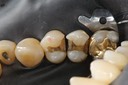

Chris Woo #14 pre-op

Chris Woo #14 caries removal

Chris Woo #14 prep